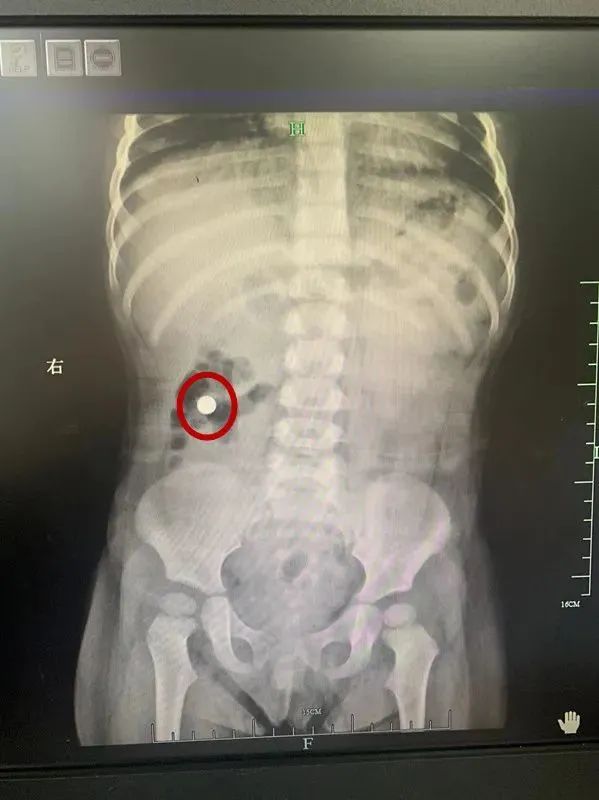

近日,淄博一位年轻的父亲抱着孩子,匆忙来到淄博市妇幼保健院急诊科,他大声呼喊着:“医生医生,快救救我的孩子,他吞了个玩具。”初步观察发现,一岁左右的孩子意识清醒,未出现喘憋、呛咳、面色青紫等情况,生命体征暂时平稳。与家属的询问中得知,孩子贪玩,不小心把汽车玩具上的小车轮吞了下去,之后就一直不吃不喝,连续哭闹。家人立即拨打了120急救电话,带着孩子赶到医院。